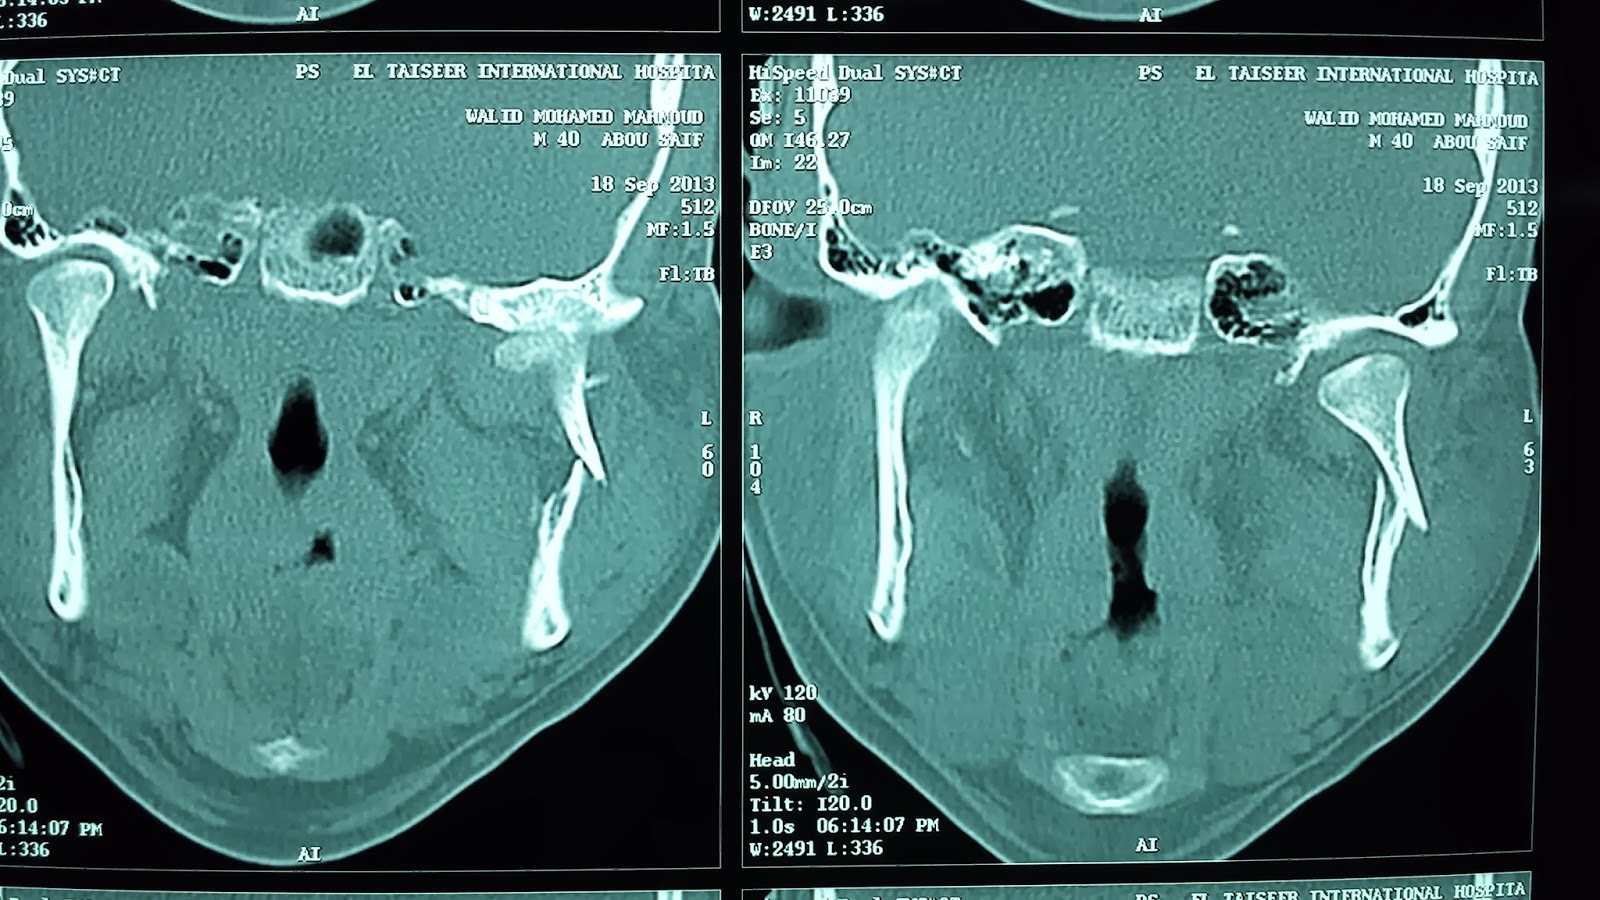

Mandibular fracture, also known as fracture of the jaw, is a break through the mandibular bone. Sectional anatomy of the mandible with frequency of fractures.

Bhagol et al developed a subcondylar fracture classification system based on ramus height shortening and the. Fractures of the mandibular condyle compose 25% to 35% of all mandible fractures. The treatment of subcondylar mandible fractures is a topic of debate and can be variable even though these fractures are commonly seen.

The one exception is the unilateral subcondylar fracture in the patient with a normal occlusion, which we shall discuss later. The following list attempts to classify subcondylar process of mandible closed fracture into categories where each line is subset of the next. Mandible fracture pdf for free. Fractures of the mandible are common.1the most commonly fractured sites are the body of the mandible, condyle, angle, symphysis, ramus and the coronoid process. Surgical management of a mandible subcondylar fracture. While mandible fractures have similar complication rates whether treated immediately or days later, older mandibulat are believed to have. Mandibular fracture, also known as fracture of the jaw, is a break through the mandibular bone. Condylar fractures require early and accurate diagnosis as well as prompt management to maximize successful osseous healing and minimize the development of future deformity. Simple fractures involving the body of the mandible can be effectively treated with one miniplate panoramic tomogram of fixation of subcondylar fracture using two miniplates; Edward ellis, robert kellman, and emre vural address questions for discussion are there specific indications for open versus closed treatment of subcondylar fractures? #rta #rodtrafficaccident #accident #fracture this young man had been involved in a motor vehicle accident approximately a month ago and had suffered a left. Bilateral subcondylar fractures are sometimes termed flail mandible, and can cause involuntary posterior movement of the tongue with subsequent obstruction of the upper airway. Endoscopic approaches to subcondylar fractures of the mandible. Although traditionally the mandible and base of skull are thought to form a complete bony ring, interrupted only by the tmjs. Download the medical book : Learn about the mandible jaw bone anatomy including parts of the mandible. A review on treatment strategies.